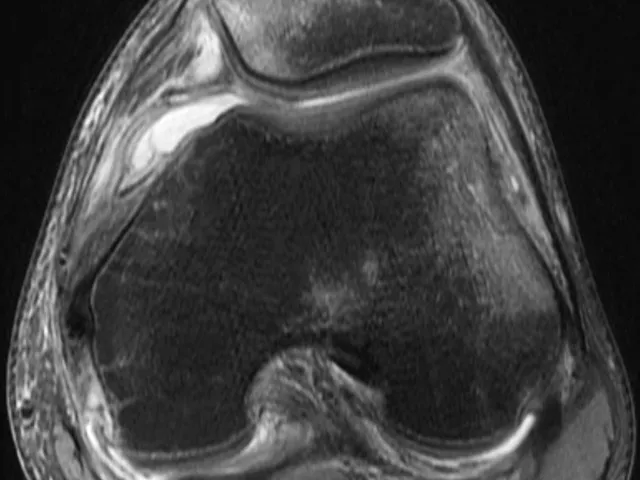

Sports Injuries MRI Fellowship - Lower extremity

This 3-day musculoskeletal imaging fellowship with MSK radiologist Dr. Phillip Tirman will help participants feel more comfortable in MR imaging of sports injuries of the lower extremity. The fellowship is interactive with a series of lectures, individual readings of select cases, and group discussions guided by the expert mentor.

The online msk radiology fellowship provides basic to advanced knowledge and will give participants an overview of the spectrum of presentations seen with sports injuries of the lower extremity. Emphasis will be placed on the multi-factorial approach to arrive at the correct diagnosis. Pelvic & groin, knee, ankle, foot, and selected lower extremity muscle and nerve injuries will be covered.